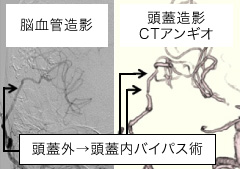

症例脳血行再建術(バイパス術)

手術前

手術前 手術後

手術後